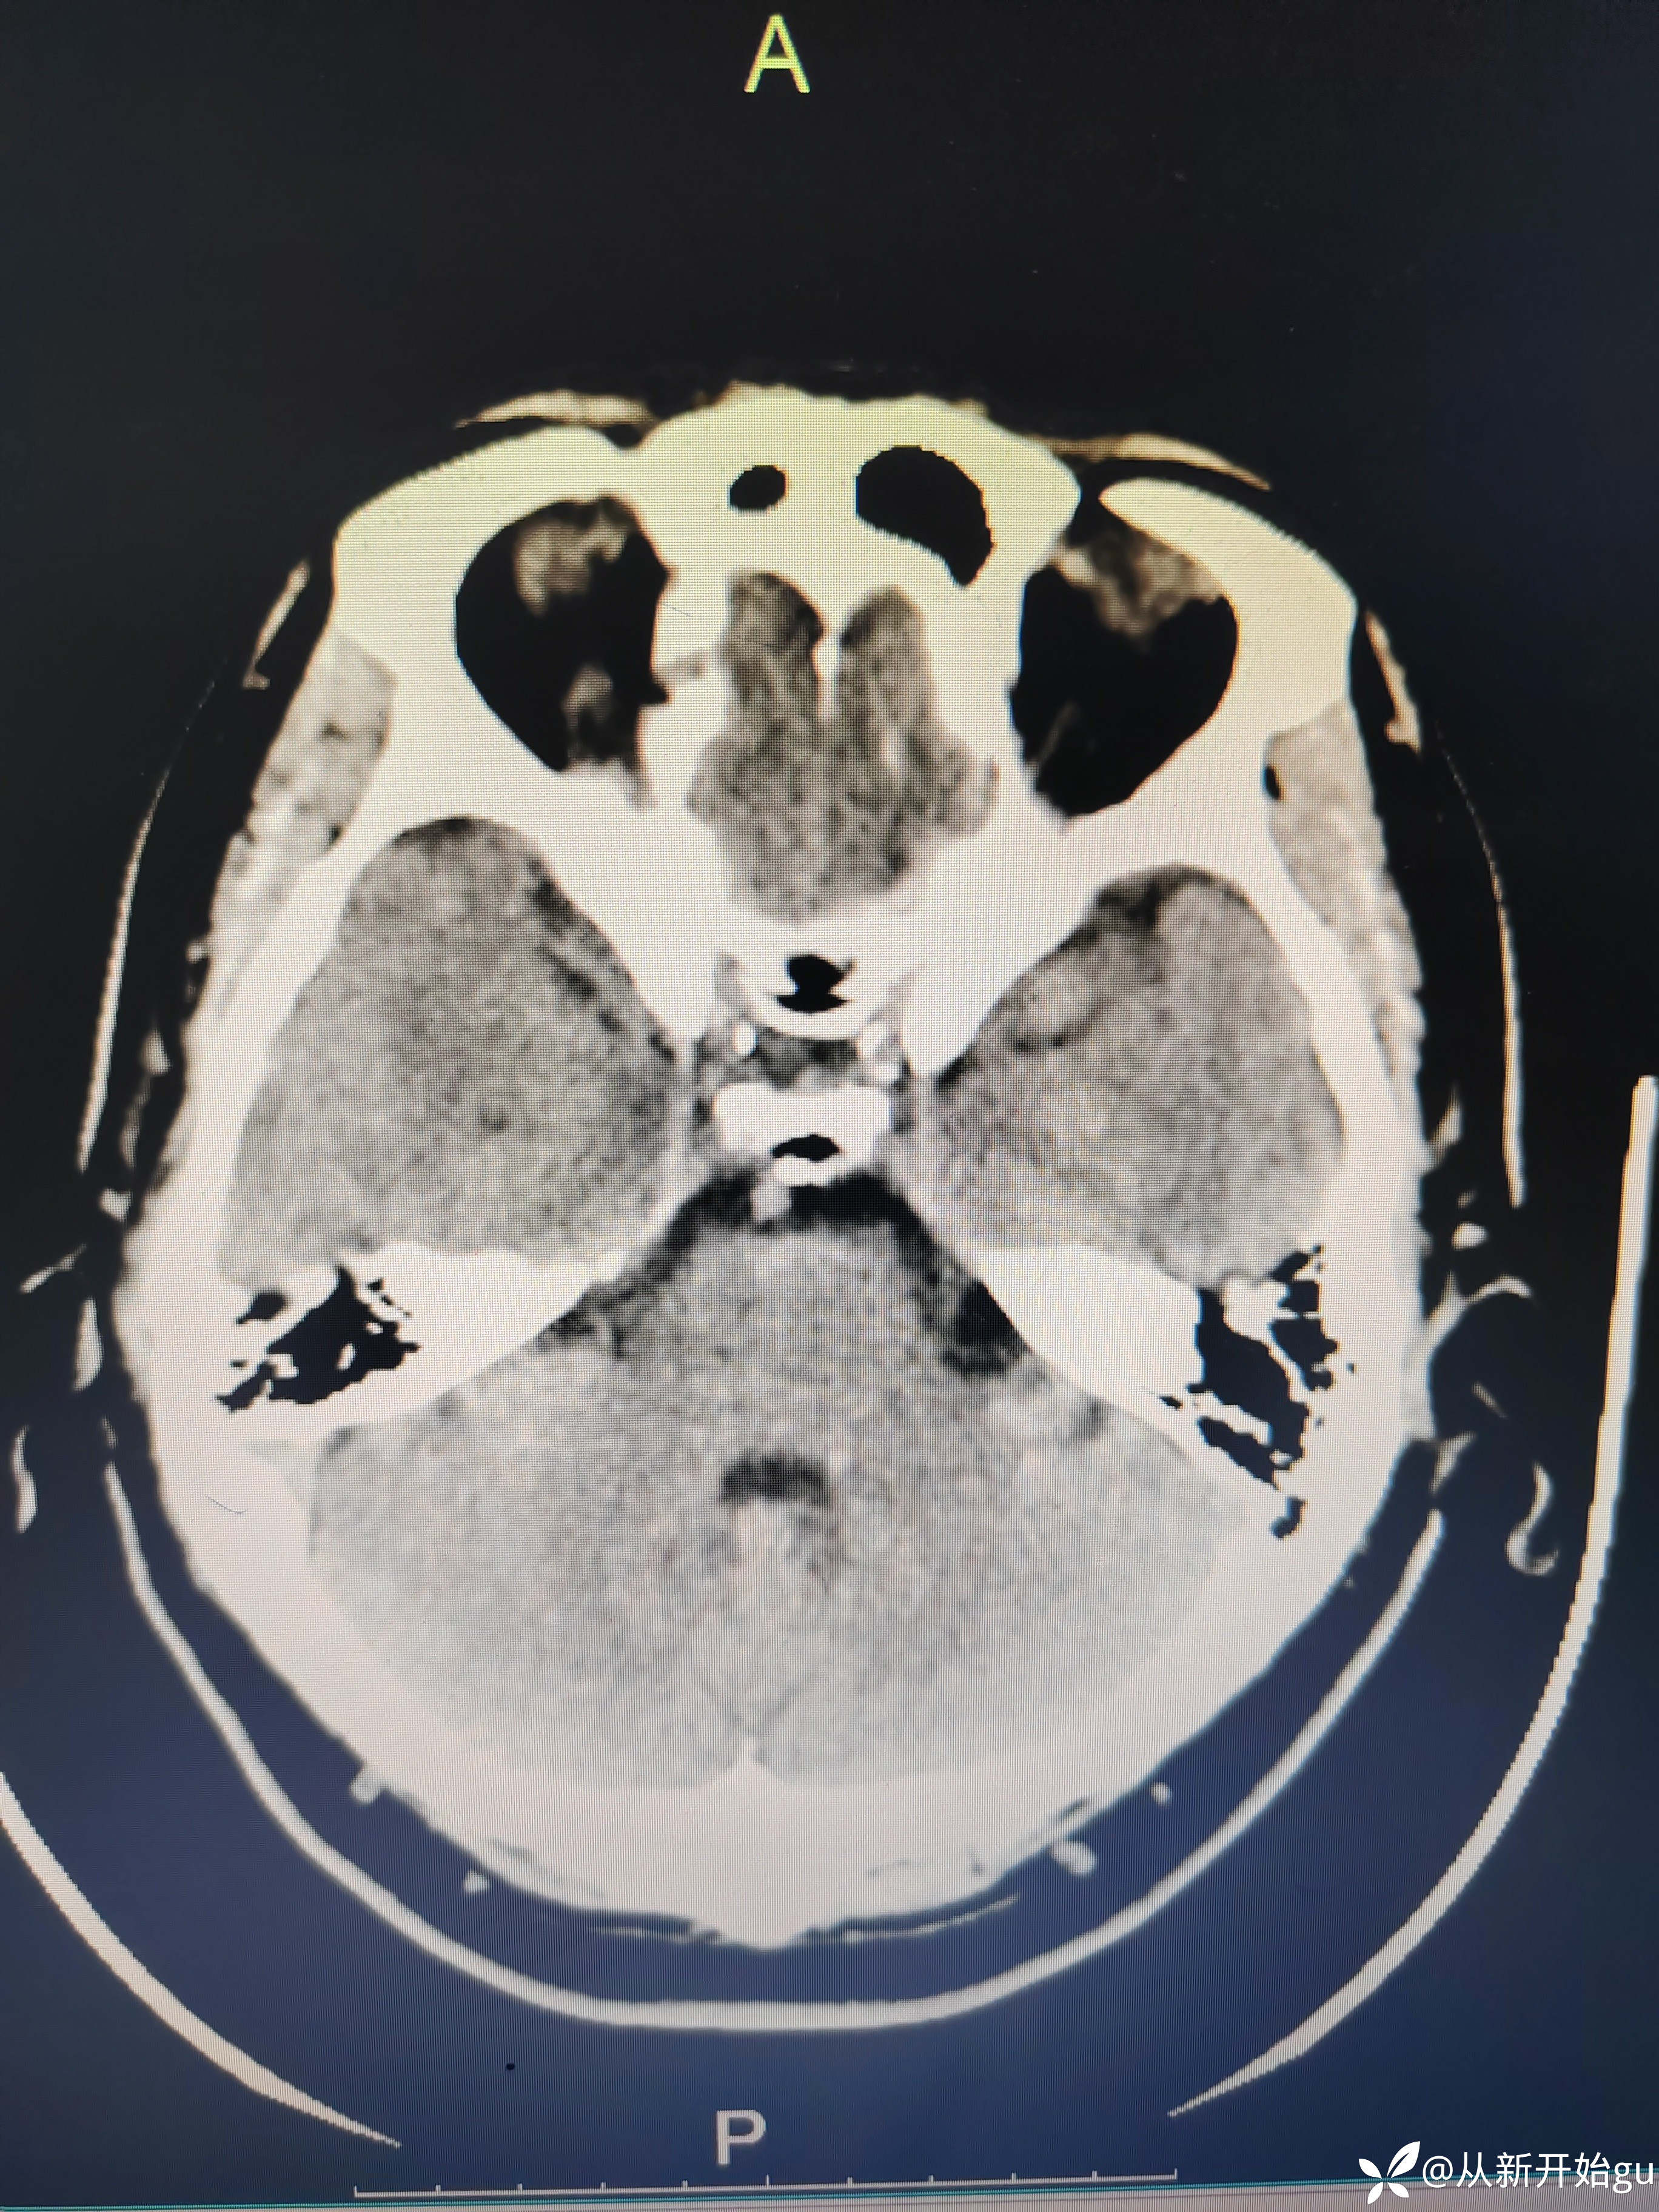

患者51岁男性,主因左下肢活动障碍1小时来院。既往高血压病史,查体,右侧鼻唇沟稍浅(家属诉之前就这样),神舌居中,左侧下肢肌力5级-,左侧跟膝胫试验欠稳准,左侧巴氏征阳性,评分也就一分,鼻唇沟稍浅未纳入。行颅脑CT检查如图所示